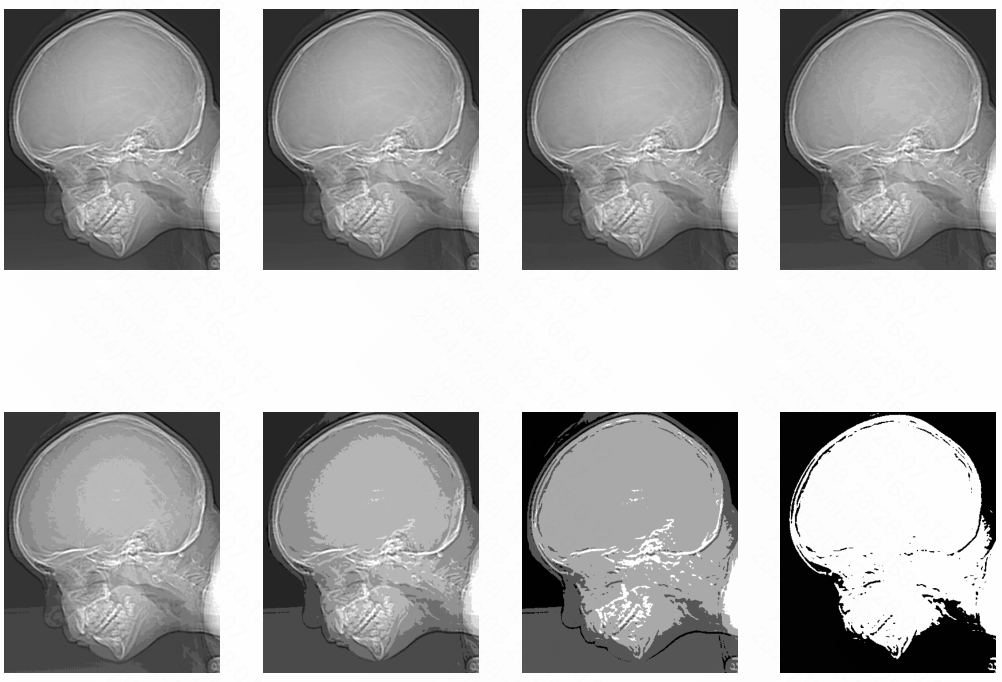

Image Sampling

- Example

1 | from skimage.transform import rescale |

The purpose of this code is to demonstrate the effects of repeatedly downscaling an image without applying any anti-aliasing filters. As the image is rescaled multiple times, the quality and resolution of the image will degrade, and the visual artifacts may become more pronounced.